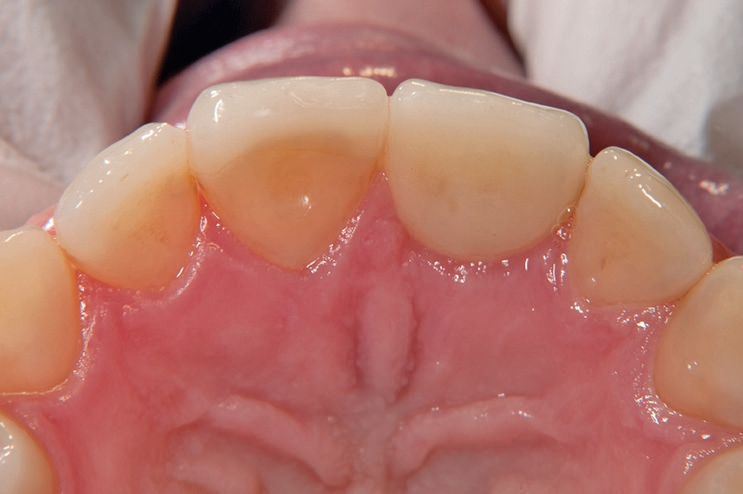

Gleichzeitig mit der prothetischen Versorgung des Implantats wurde auch für Zahn 11 ein Veneer geplant. Zum Einsatz kam ein Zeramex T Implantat Durchmesser 5,5 mm, Länge 12 mm. Für die Kronenversorgung wurde ein mit e. Max überpresstes CAD-Abutment gewählt. Während der Einheilphase des Implantats kam eine Sunflex-Prothese zum Einsatz.